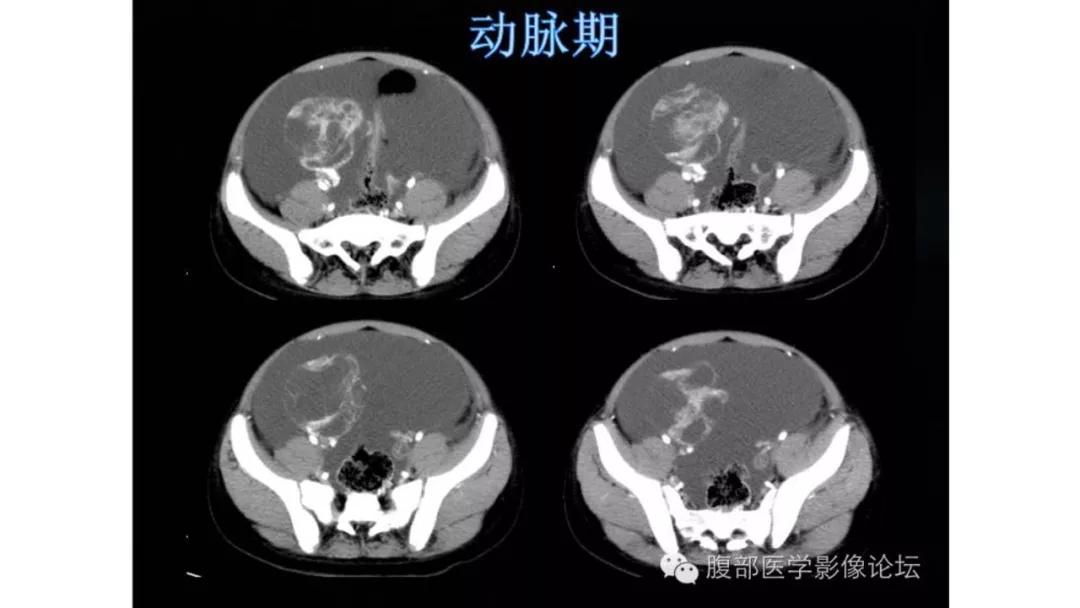

病理:颗粒细胞瘤

- 良性及低恶肿瘤强化往往比较轻度,高恶肿瘤强化往往比较快而明显,也就是说,迅速、明显强化的卵巢肿瘤往往代表高度恶性

- 囊实性无壁结节:最常见于颗粒细胞瘤